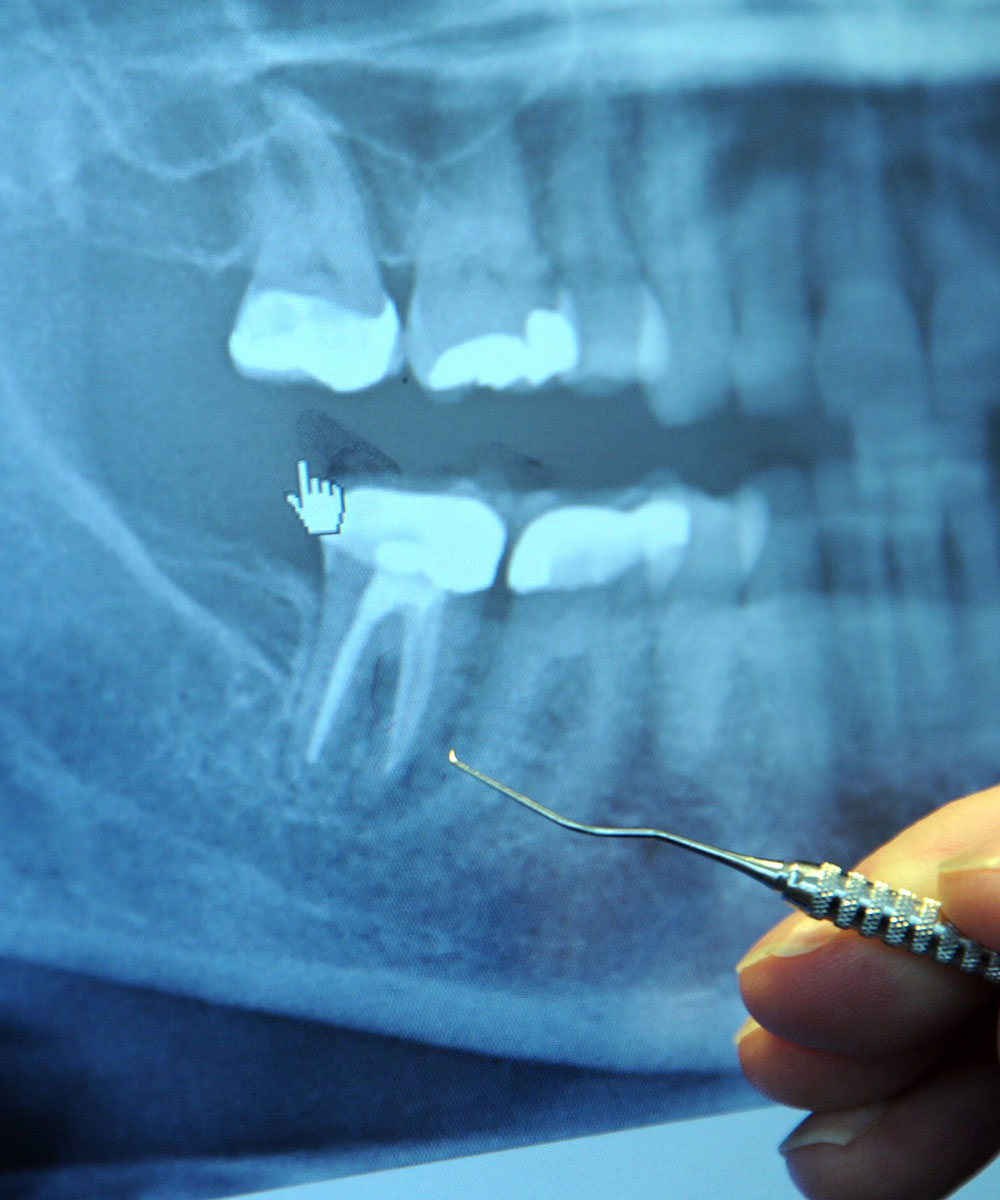

Radiographs (x-ray pictures) allow dentists to diagnose and treat problems not yet visible to the naked eye, including early tooth decay, gum disease, abscesses and abnormal growths. There is no question that since x-rays first became available a century ago, this diagnostic tool has prevented untold suffering and saved countless teeth. Now, state-of-the-art digital x-rays have made the technology even safer and more beneficial.

Digital x-ray technology uses a small electronic sensor placed in the mouth to capture an image, which can be called up instantly on a computer screen. When digital x-rays first became available about 20 years ago, they immediately offered a host of advantages over traditional x-ray films, which require chemical processing. Most importantly, they cut the amount of radiation exposure to the dental patient by as much as 90%. While faster x-ray films have been developed over the years that require less exposure, making that difference less dramatic, a digital x-ray still offers the lowest radiation dose possible.

- A clearer picture. It’s possible to get more information from digital x-rays because they are sharper and can be enhanced in a number of ways. The contrast can be increased or decreased, and areas of concern can be magnified. It’s even possible to compare them on-screen to your previous x-rays, making even the minutest changes to your tooth structure easier to detect.